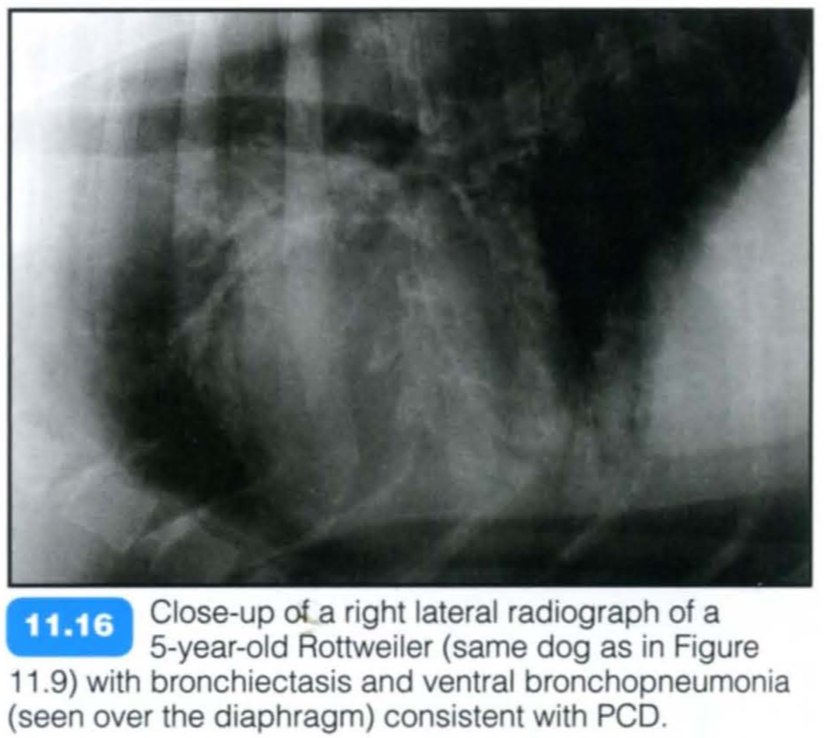

Primary ciliary dyskinesia (PCD), also known as immotile cilia syndrome, is a diverse group of inherited structural and functional abnormalities of the respiratory and other cilia, which results in recurrent respiratory tract infections in the dog. More specifically, PCD is an inherited defect in microtubule formation, affecting cilia of the respiratory and urogenital tract and the auditory canal.

Typically PCD is diagnosed in young purebred animals with a reported higher incidence in the Bichon Frise. The condition may be seen in mixed breed dogs and also in cats.

There is a relatively high prevalence of a respiratory disease and the phenotype is almost identical to PCD in humans. The respiratory manifestations include chronic rhinitis , bronchitis and severe pneumonia with or without bronchiectasis. Affected animals are presented with recurrent chronic nasal discharge, productive cough, respiratory distress and exercise intolerance. Additional findings are infertility, hydrocephalus and loss of hearing.

Radiography: